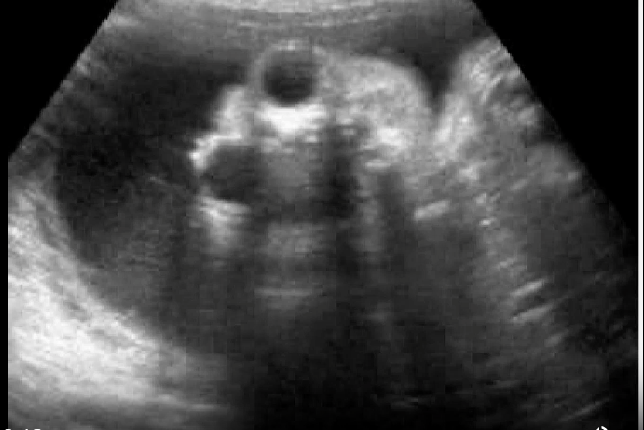

what maternal serum level will be increased

this is frog eyes aka anencephaly

a) inhibin A

b) estriol

c) delta OD450

d) AFP